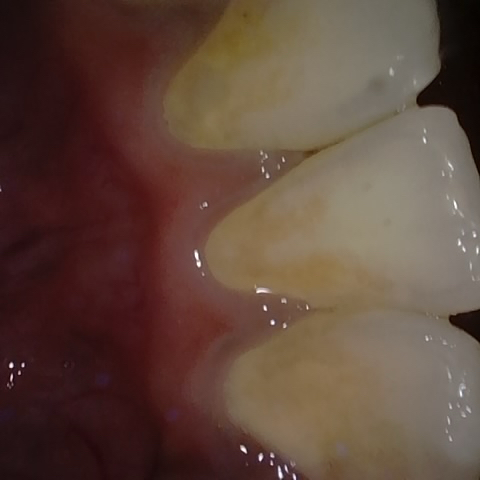

Annotated as "Good"